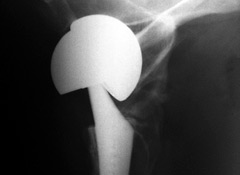

If any patient should have gone into a hip replacement fully informed, it was Stephen Tower, M.D., 55, an orthopedic surgeon from Anchorage, Alaska. Instead, he became the victim of another device that was grandfathered onto the market without clinical testing.

In this case, it was an artificial hip introduced in 2005 by DePuy, the orthopedic division of Johnson & Johnson. Called the ASR XL (shown at the top of this page), it was distinctive because both components—the ball at the top of the femur and the socket liner inside the pelvis—were made of chrome-cobalt metal.

The FDA cleared it without clinical testing based on “substantial equivalence” to earlier devices, though such metal-on-metal hips had long been on the agency’s high-priority list for requiring advance clinical trials.